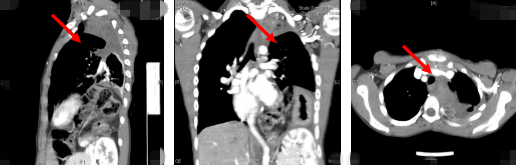

清华长庚医院8月24日电(神经外科  杨峰)如图中所示,本是正常人心脏、左肺的位置,被发于神经鞘的巨大肿瘤占据,导致一位刚满12岁的男孩胸痛、咳嗽、呼吸困难。近日,北京清华长庚医院神经外科与胸外科联手,由神经外科王贵怀主任主刀,成功为男孩切除胸腔巨大神经鞘肿瘤。

半年前,患者经常会出现胸痛、咳嗽和呼吸困难,在当地医院检查发现左侧胸腔巨大占位,左肺及心脏明显受压。北京清华长庚医院王贵怀主任接诊,仔细查体了解病情,并反复认真阅片后,认为左侧胸腔巨大肿瘤来自于胸椎椎管内,神经鞘瘤可能性大,该肿瘤体积巨大,占据绝大部分胸腔空间,压迫左肺、纵隔大血管及膈肌。

患者术后复查影像显示体内肿瘤已切除